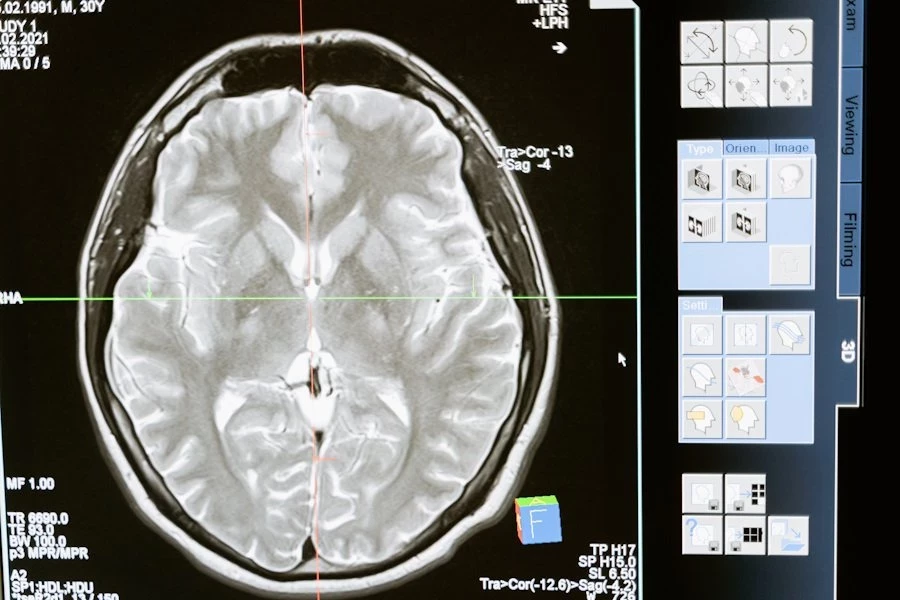

Нейробиологи РФ работают над созданием нейроинтерфейса, помогающем улучшить реакции у пожилых людей. Их исследования основаны на использовании транскраниальной магнитной стимуляции, или ТМС, сообщает ТАСС.

ТМС — это метод, при котором магнитные поля воздействуют на активные участки мозга. Этот метод может быть полезен в реабилитации после травм двигательного аппарата. Нейробиологи утверждают, что ТМС способствует активизации мозговой деятельности.